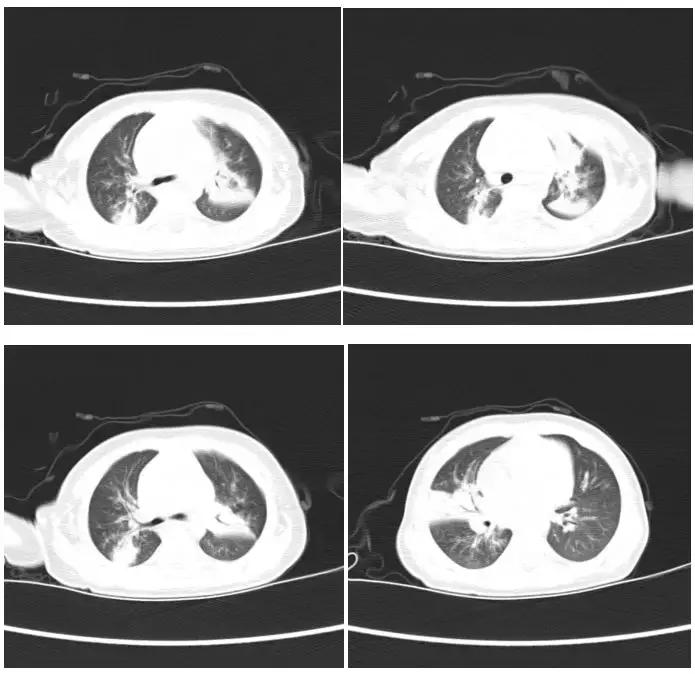

患儿7个月小宝,因发热、咳嗽在外院治疗7天无好转,来罗湖医院就诊,入院后根据患儿症状体征辅助检查肺炎支原体阳性,肺部CT提示两肺多发肺炎,两上肺及右肺中叶明显。